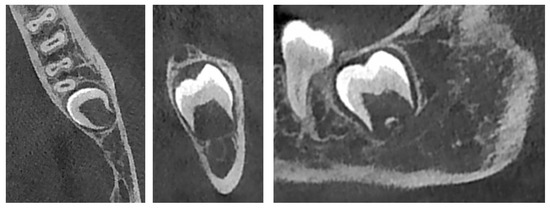

2.2. CBCT Evaluation of the DFs

3.2. CBCT and Histological Evaluation of the DFs